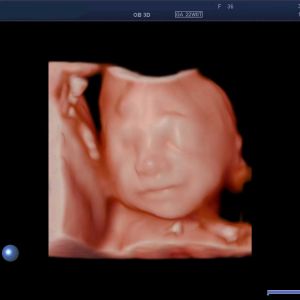

Beurteilt werden Aussehen und Funktion aller sichtbaren Organe des Ungeborenen und weitere Faktoren wie Wachstum, Fruchtwassermenge, Blutfluss in der Nabelschnur, Lage und Aussehen des Mutterkuchens (Plazenta) sowie dessen Durchblutung. Die 3D/4D-Darstellung kann bei bestimmten Fragestellungen ergänzende Informationen liefern.